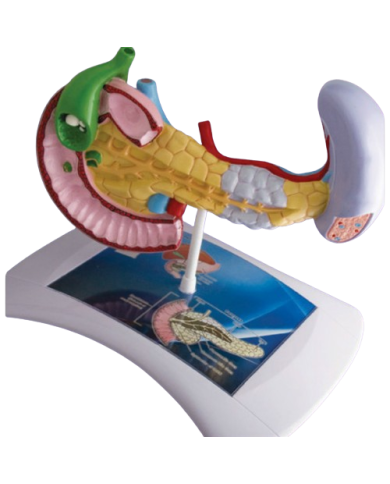

Modello anatomico PER FORNITURE CASE FARMACEUTICHE

Modello anatomico PER FORNITURE CASE FARMACEUTICHE

Modello anatomico PER FORNITURE CASE FARMACEUTICHE

Modello anatomico PER FORNITURE CASE FARMACEUTICHE

Modello anatomico PER FORNITURE CASE FARMACEUTICHE

Modello anatomico PER FORNITURE CASE FARMACEUTICHE

Modello anatomico PER FORNITURE CASE FARMACEUTICHE

Modello anatomico PER FORNITURE CASE FARMACEUTICHE

Modello anatomico PER FORNITURE CASE FARMACEUTICHE

Modello anatomico PER FORNITURE CASE FARMACEUTICHE

Modello anatomico PER FORNITURE CASE FARMACEUTICHE

Modello anatomico PER FORNITURE CASE FARMACEUTICHE

Modello anatomico PER FORNITURE CASE FARMACEUTICHE

Modello anatomico PER FORNITURE CASE FARMACEUTICHE

Modello anatomico PER FORNITURE CASE FARMACEUTICHE

Modello anatomico PER FORNITURE CASE FARMACEUTICHE

Modello anatomico PER FORNITURE CASE FARMACEUTICHE

Modello anatomico PER FORNITURE CASE FARMACEUTICHE

Modello anatomico PER FORNITURE CASE FARMACEUTICHE

Modello anatomico PER FORNITURE CASE FARMACEUTICHE

Modello anatomico PER FORNITURE CASE FARMACEUTICHE

Modello anatomico PER FORNITURE CASE FARMACEUTICHE